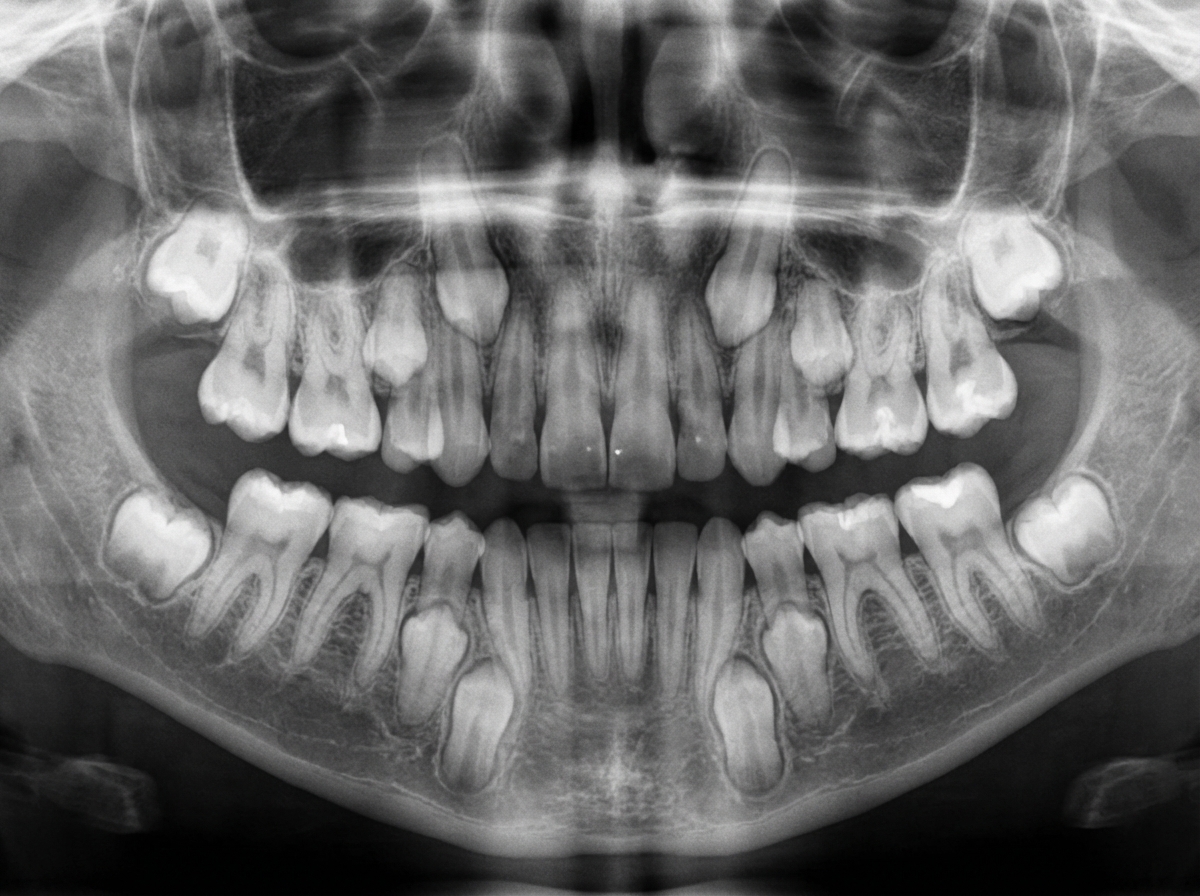

What is the estimated age of this individual?

Explanation: ***8 years*** - This age corresponds to the **mixed dentition stage** where **first permanent molars** and **central incisors** are erupted, with **lateral incisors** beginning to erupt. - **Deciduous canines** and **primary molars** are typically still retained at this age, following **Schour and Massler** developmental milestones. *6 years* - At 6 years, only the **first permanent molars** ("6-year molars") and possibly **central incisors** would be erupting. - The **mixed dentition** pattern would be less developed compared to what's observed in this case. *10 years* - By 10 years, **lateral incisors** would be fully erupted and **canines** and **premolars** would be actively erupting. - The **deciduous teeth** would show more advanced **exfoliation** patterns than seen here. *17 years* - At 17 years, all **permanent teeth** except **third molars** would be present and fully erupted. - This represents **permanent dentition** stage, not the **mixed dentition** pattern observed in this individual.